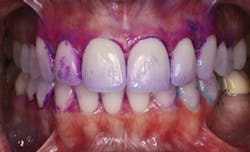

Bacterial testing is also available to test for the presence of Streptococcus mutans and Lactobacillus.19 Although these tests are useful, it may also be time-consuming for a dental hygienist to implement this type of testing on every patient. The dental hygienist is the ideal dental practitioner to evaluate the presence, location, and amount of plaque and calculus on the teeth. In addition, a disclosing agent (see Fig. 1) designed to detect acidogenic dental plaque (see Fig. 2)20 may be an efficient, cost-effective alternative.